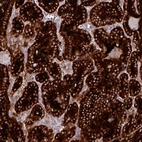

Immunohistochemistry analysis in human thyroid gland and liver tissues using AMAb90523 antibody. Corresponding TG RNA-seq data are presented for the same tissues.